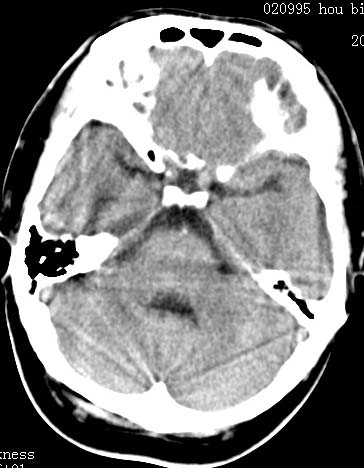

以下是引用clj20在2007-8-29 9:47:00的发言:[br]蛛网膜下腔出血,左侧额叶不均匀密度影,占位效应明显,界限不清。支持:占位性病变,建议增强!

以下是引用xulianj在2007-8-29 20:15:00的发言:[br]蛛网膜下腔出血,左侧额叶不均匀密度影,占位效应明显,界限不清。支持:占位性病变,建议增强!

以下是引用jiangjing在2007-8-29 14:33:00的发言:[br]左侧额叶不均匀密度影[低密度为主,边缘见等密度环环绕]占位效应明显,界限不清。支持:占位性病变,建议增强! [br][br]